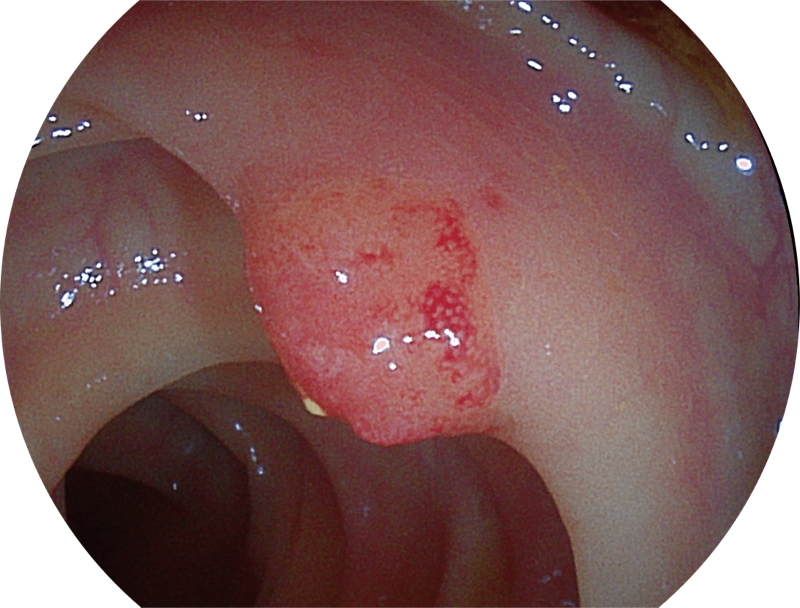

能够凸显黏膜浅层血管轮廓和黏膜表面微结构,适用于中、近景观察下的早癌精确诊断。

百万级像素高清传感器,1080P全高清视频信号输出,图像清晰。